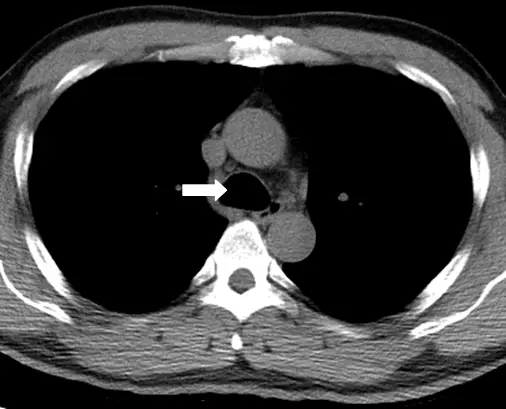

下圖為胸部電腦斷層攝影,白色箭號所顯示解剖構造為:

胸部電腦斷層(chest CT)橫斷面(axial)影像上,縱膈腔(mediastinum)各結構的辨識——特別是氣管(trachea)的特徵性外觀。

影像分析:

本題影像為胸部 CT 橫斷面,可見縱膈腔中央有多個結構:

- 白色箭號所指:位於縱膈腔中央偏右的一個圓形/卵圓形低密度(黑色)結構,內含空氣,邊緣可見薄層軟組織(氣管軟骨環)。此為氣管(trachea)的典型外觀——管腔充滿空氣(CT 值接近 -1000 HU),因此呈現極低密度的黑色。

- 周圍圓形高密度(灰白)結構:為大血管(主動脈弓分支等),在非增強 CT 呈軟組織密度,增強 CT 則充填對比劑而明顯強化。

- 脊椎前方:可見椎體為高密度骨骼結構。

- 兩側:為充氣的肺野(低密度)。

關鍵辨識:白色箭號指向的結構內部為空氣(極低密度),這是辨識氣管最直接的特徵。